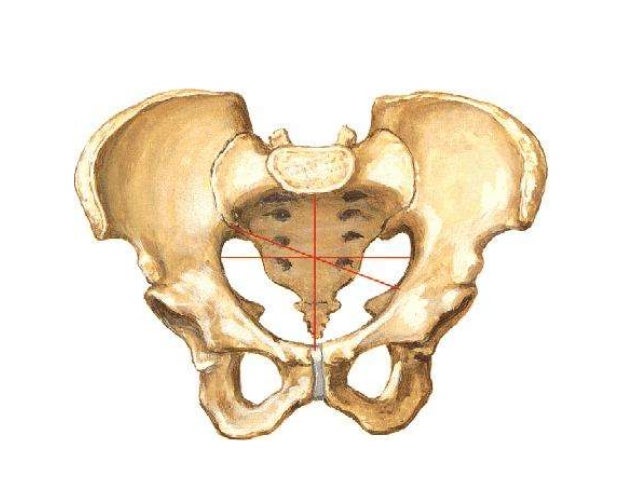

Анатомия малого таза: детальные схемы и изображения